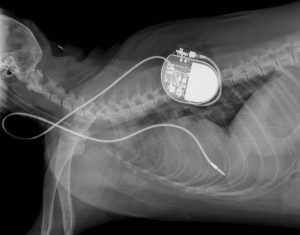

Auf diesem Röntgenbild sieht man Jackys Herzschrittmacher. (Foto: -/Medizinische Kleintierklinik der LMU)

Ein Tierarzt setzte Jacky einen Herz-Schritt-Macher ein. Das ist ein technisches Gerät, das kranke Herzen im richtigen Tempo schlagen lässt. Zuvor hatte der Tierarzt bereits vielen Hunden so ein Gerät eingesetzt.